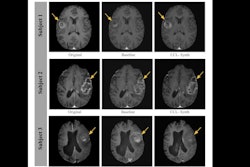

The team used their method to reconstruct the (Magnetom, Siemens Healthineers) scans of 15 healthy volunteers and three people with MS. Alyuz reported satisfactory image quality and accuracy in both groups, adding that the multicontrast MR images demonstrated successful reconstruction of pathological details related to MS.

"The only clear degradation was in the white matter, which might indicate that our model was sensitive to the lesions, but this might be explained by the lack of MS patients in the training data," Alyuz said.